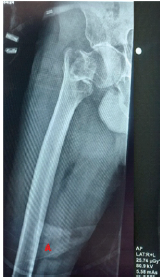

Uncoupling of the Helical Blade in a Proximal Femoral Nail – A Novel Mechanical Failure

Anurag Bhakhar , Anil Kumar , Bhaskar Sarkar , Nirvin Paul , Arvind Kumar Yadav , Md. Quamar Azam

………………………………p.204-209